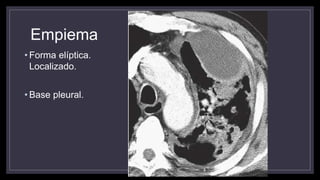

Empiema

• Se utiliza su termino cuando el derrame pleural se infecta y existe pus

• Sospecha cuando la clínica de una neumonía persiste y no mejora

• 75% son por bacterias anaerobias o cultivos mixtos

• Bajos niveles de glucosa (menor a 40 mg/dl)

• pH menor a 7.20

• Un derrame pleural localizado en paciente con neumonía sugiere la

formación de un empiema

• Un empiema puede contener aire y se puede confundir con un absceso

en una placa convencional.

• Se observa en la TC

• Forma lenticular o elíptica

• Son localizados

• Bordes lisos uniformes BIEN DEFINIDOS

• Con contraste realzan los bordes de la pleura parietal y visceral

• Puede observarse mayor atenuación de grasa extrapleural

• Forma elíptica.

Localizado.

• Base pleural.